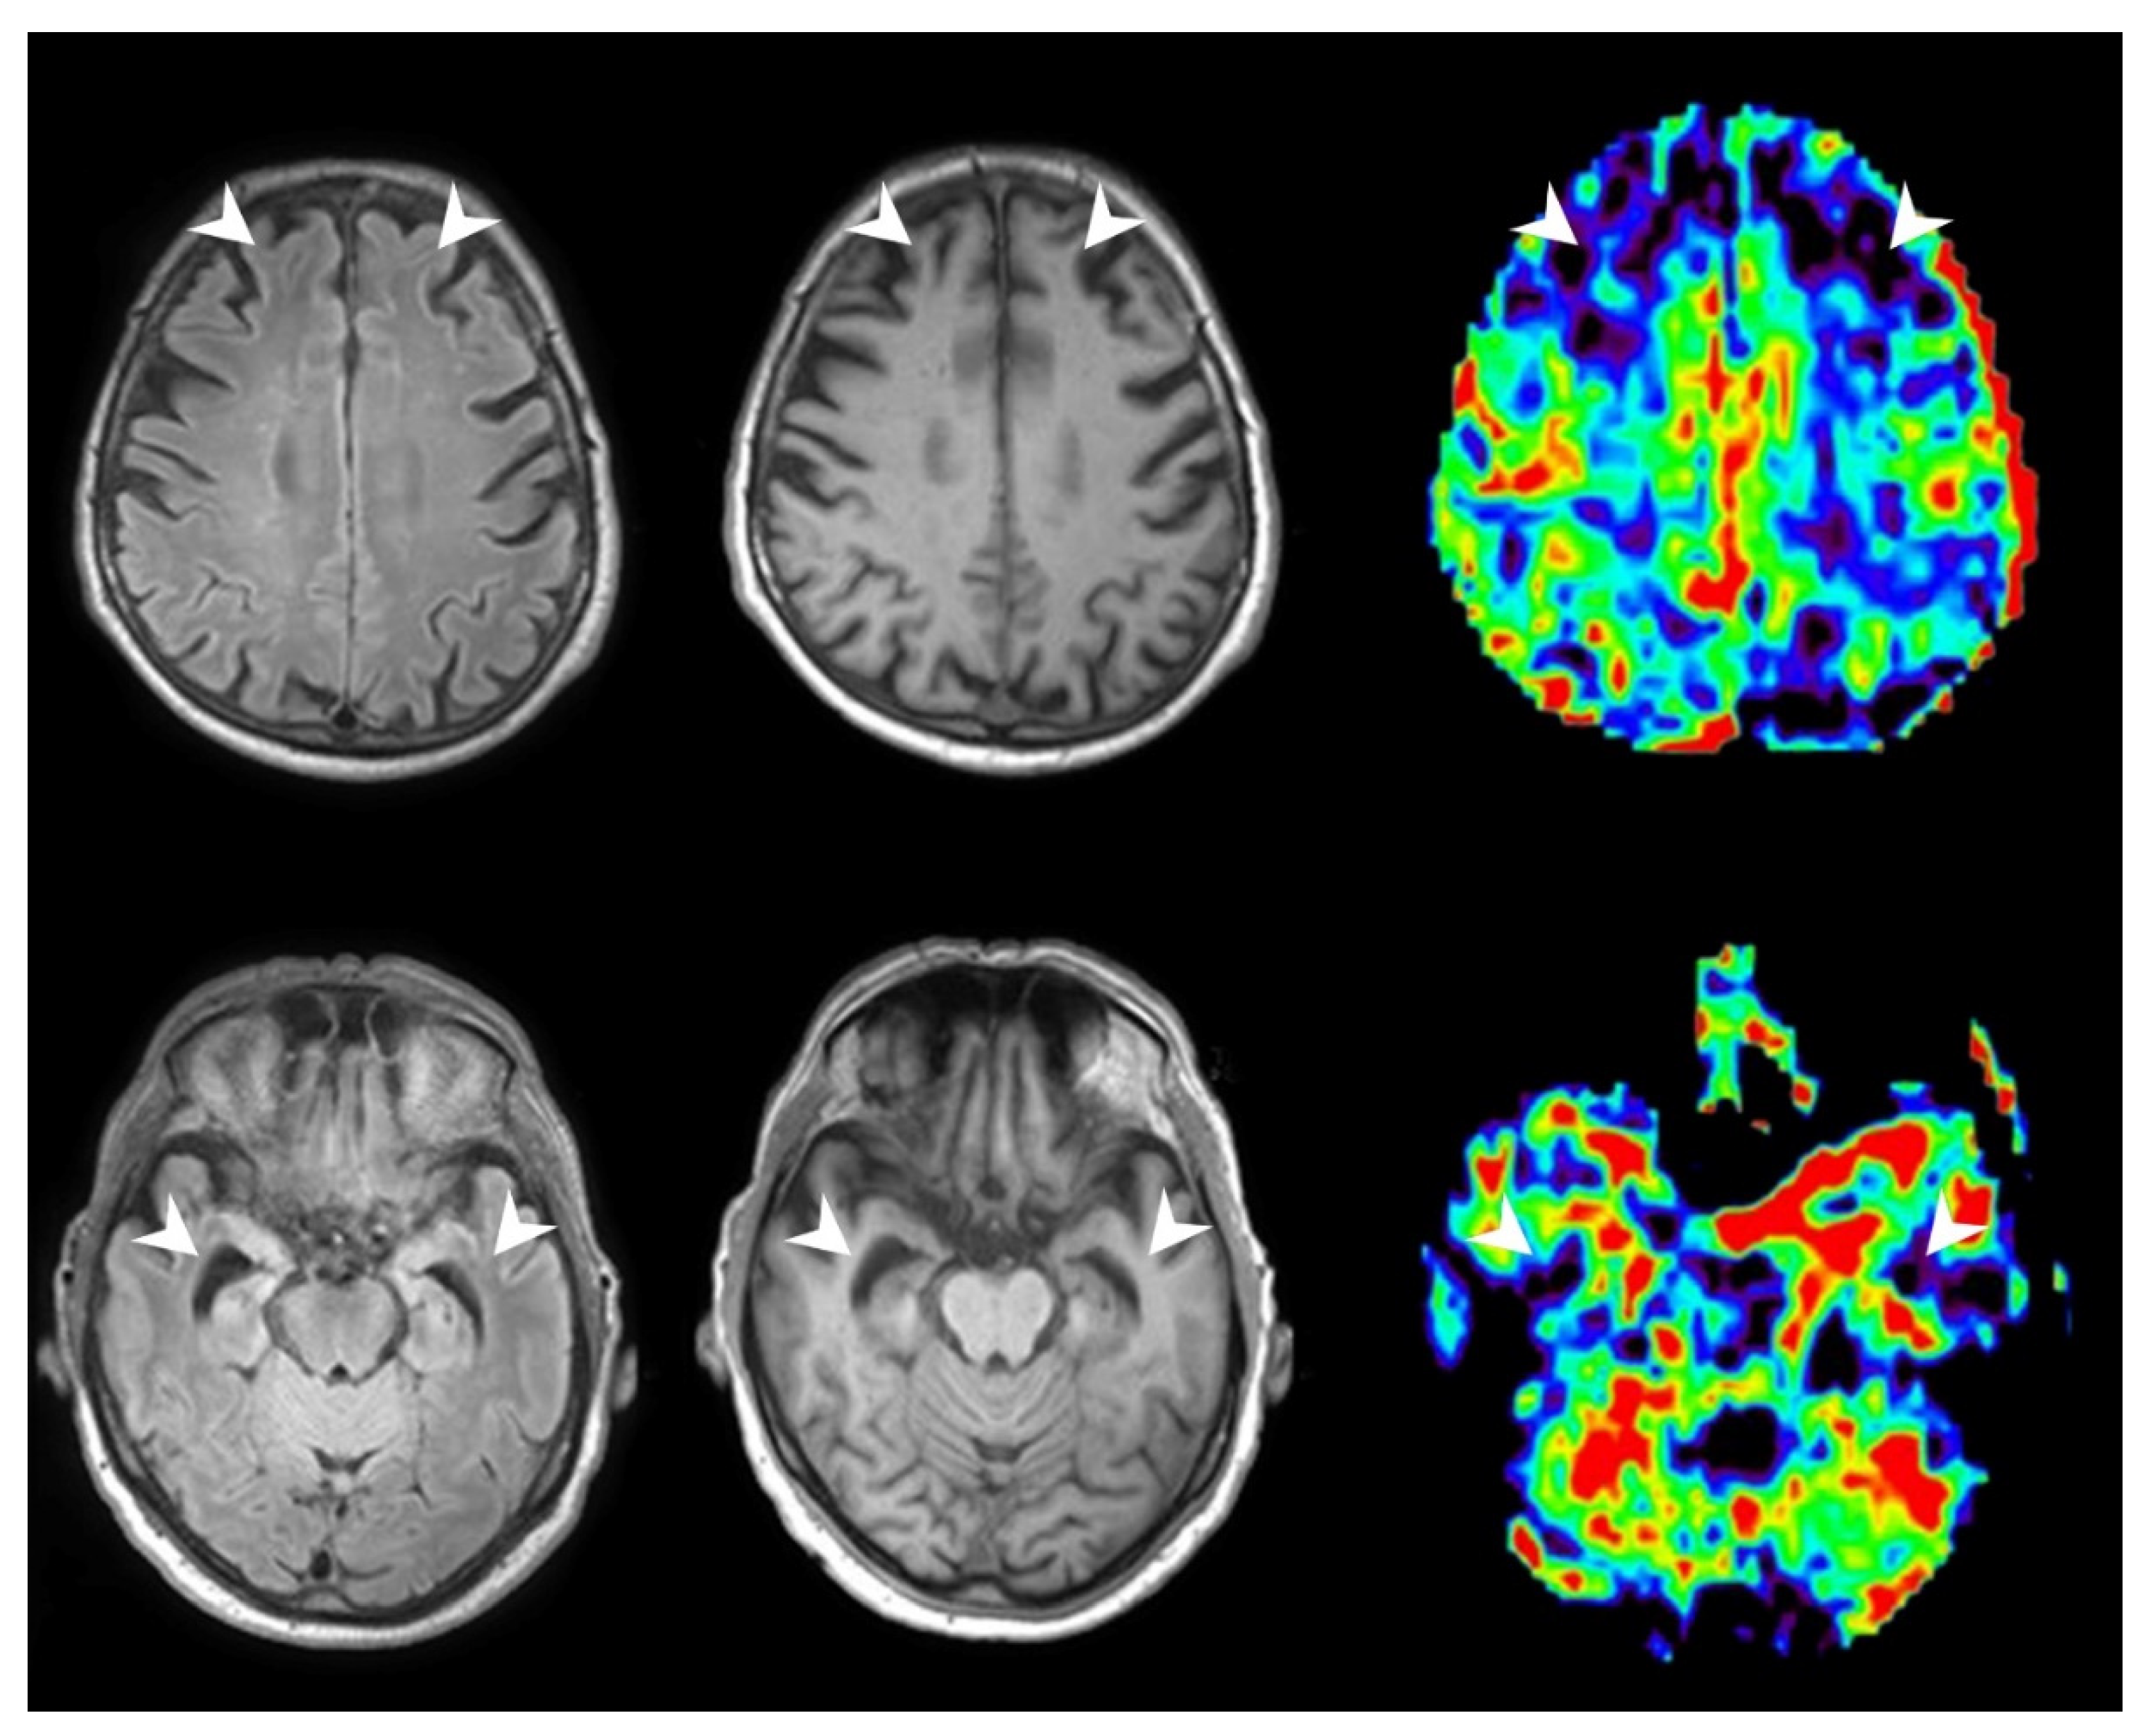

3.2.2. Patients with MCI